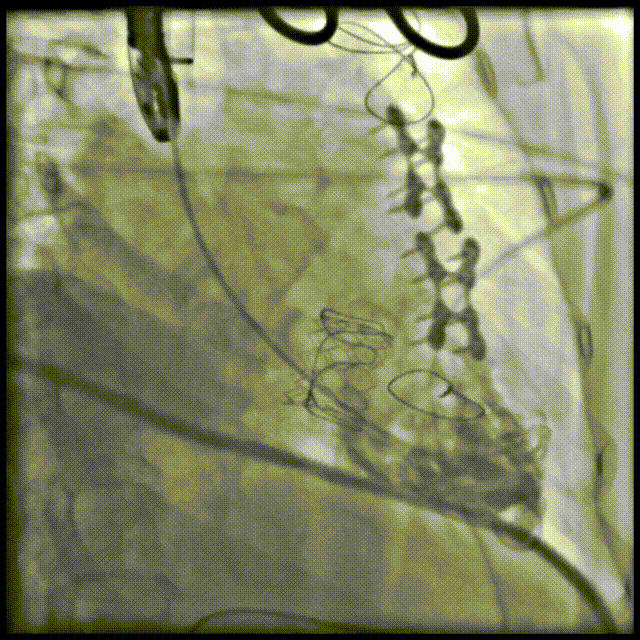

三尖瓣病例:

患者女性,62岁,既往三尖瓣位植入29# SAV猪瓣,超声提示三尖瓣人工瓣膜衰败,压差升高伴重度关闭不全。患者合并房颤伴长间歇、巨大右房、右心功能差,经独立专家委员会评判该患者属于外科手术高风险。术前经详尽影像学测量及多学科讨论,反复模拟分别经股静脉及经颈静脉入路输送瓣中瓣至三尖瓣的角度后,发现经右侧颈静脉入路瓣膜输送角度更理想。

手术顺利,经右颈静脉入路成功植入27号Renato球扩式瓣中瓣。瓣膜植入位置理想,无瓣周漏及中央返流。经查阅现有资料,经颈静脉路径成功完成三尖瓣“瓣中瓣”治疗在国内尚属首例。

▲球扩三尖瓣 ▲右室造影